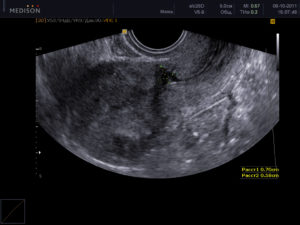

Выявление состояния рубца

Чтобы выявить какой характер у рубца, врачи назначают инструментальную диагностику. Само образование, обычно, выявляется на УЗИ. Помимо этого, на ультразвуковых исследованиях видно, какая толщина стенки в области рубца. Это помогает узнать его форму и размеры. На УЗИ можно узнать есть ли на нем участки, которые еще не срослись.

ВАЖНО! Во время беременности может произойти истончение рубца. Поэтому, на протяжении всего периода вынашивания плода, после выявления рубца, беременные постоянно проходят УЗИ контроль.

Важным фактором при родах имеют болевые ощущения роженицы и вид кровянистых выделений. Если женщину тошнит, у нее началась рвота и появились боли в районе пупка, то следует заподозрить разрыв рубца. УЗИ помогает выяснить состояние.

Диагностировать повреждения можно при помощи ультразвукового исследования, методом пальпации, на томографии разного вида. При этом каждый способ имеет свои плюсы. Так, во время УЗИ врач может оценить положение рубца, его размер и толщину.